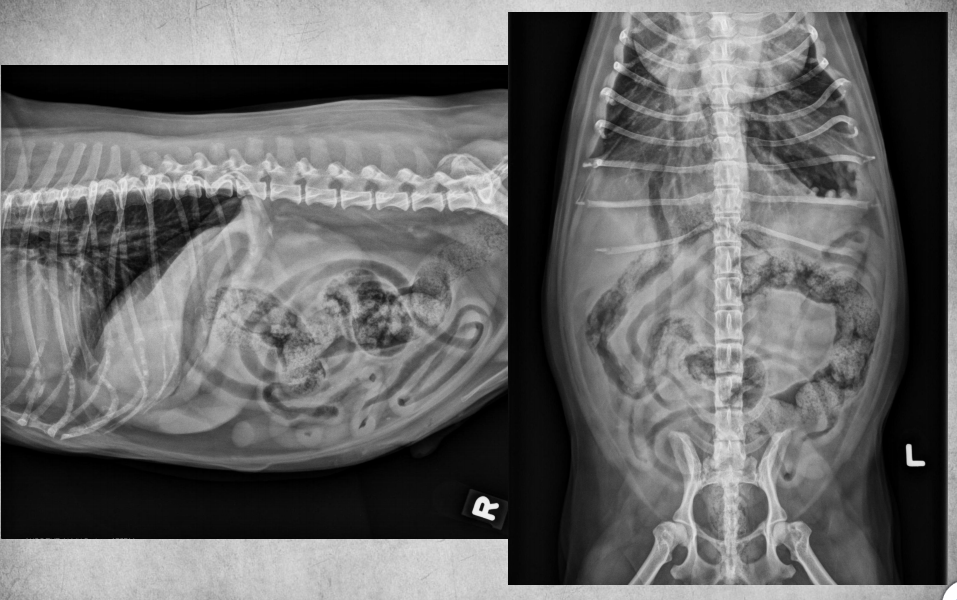

● 7 yo castrated male Golden

Retriever

● Lethargy for last 24h

fat along cranioventral aspect of thorax, maybe fluid too at heart apex.

pericardial effusion: very round heart margin tells you its fluid and not just cardiomegaly.

mild bronchial pattern

● 12 yo male castrated Shih-Tzu

● Geriatric check-up

● No clinical signs

congenital peritoneal-pericardial diaphragmatic hernia

these intestines are filled with gas due to

being empty

gastric axis also altered